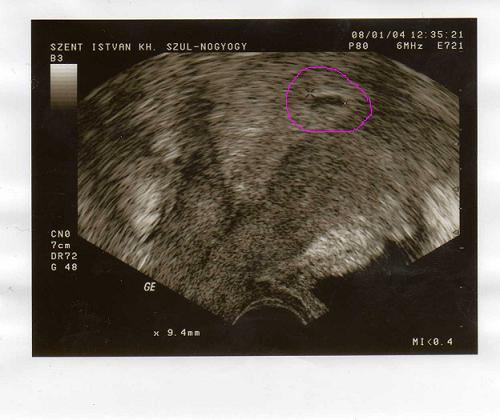

Ez a jóhír. Itt van a picim. A rossz hír hogy egy kicsit szabálytalan szélű így a doki mised ab gyanút írt a papírra mert fél hogy üres. Én mint ha láttam volna pulzálást de ő azt mondta hogy még nem látni benne semmit. Tudom kicsi még. Amúgy a petezsák 9 mn-es. Lehet hogy a tp miatt írta rá a fenyegető vetélést? Passz. de az tuti hogy nem fogok péntekig várni hanem kedden elmegyek az sztkba és ha nőtt meg ilyesmi akkor megnyugszom

Ez a jóhír. Itt van a picim. A rossz hír hogy egy kicsit szabálytalan szélű így a doki mised ab gyanút írt a papírra mert fél hogy üres. Én mint ha láttam volna pulzálást de ő azt mondta hogy még nem látni benne semmit. Tudom kicsi még. Amúgy a petezsák 9 mn-es. Lehet hogy a tp miatt írta rá a fenyegető vetélést? Passz. de az tuti hogy nem fogok péntekig várni hanem kedden elmegyek az sztkba és ha nőtt meg ilyesmi akkor megnyugszom